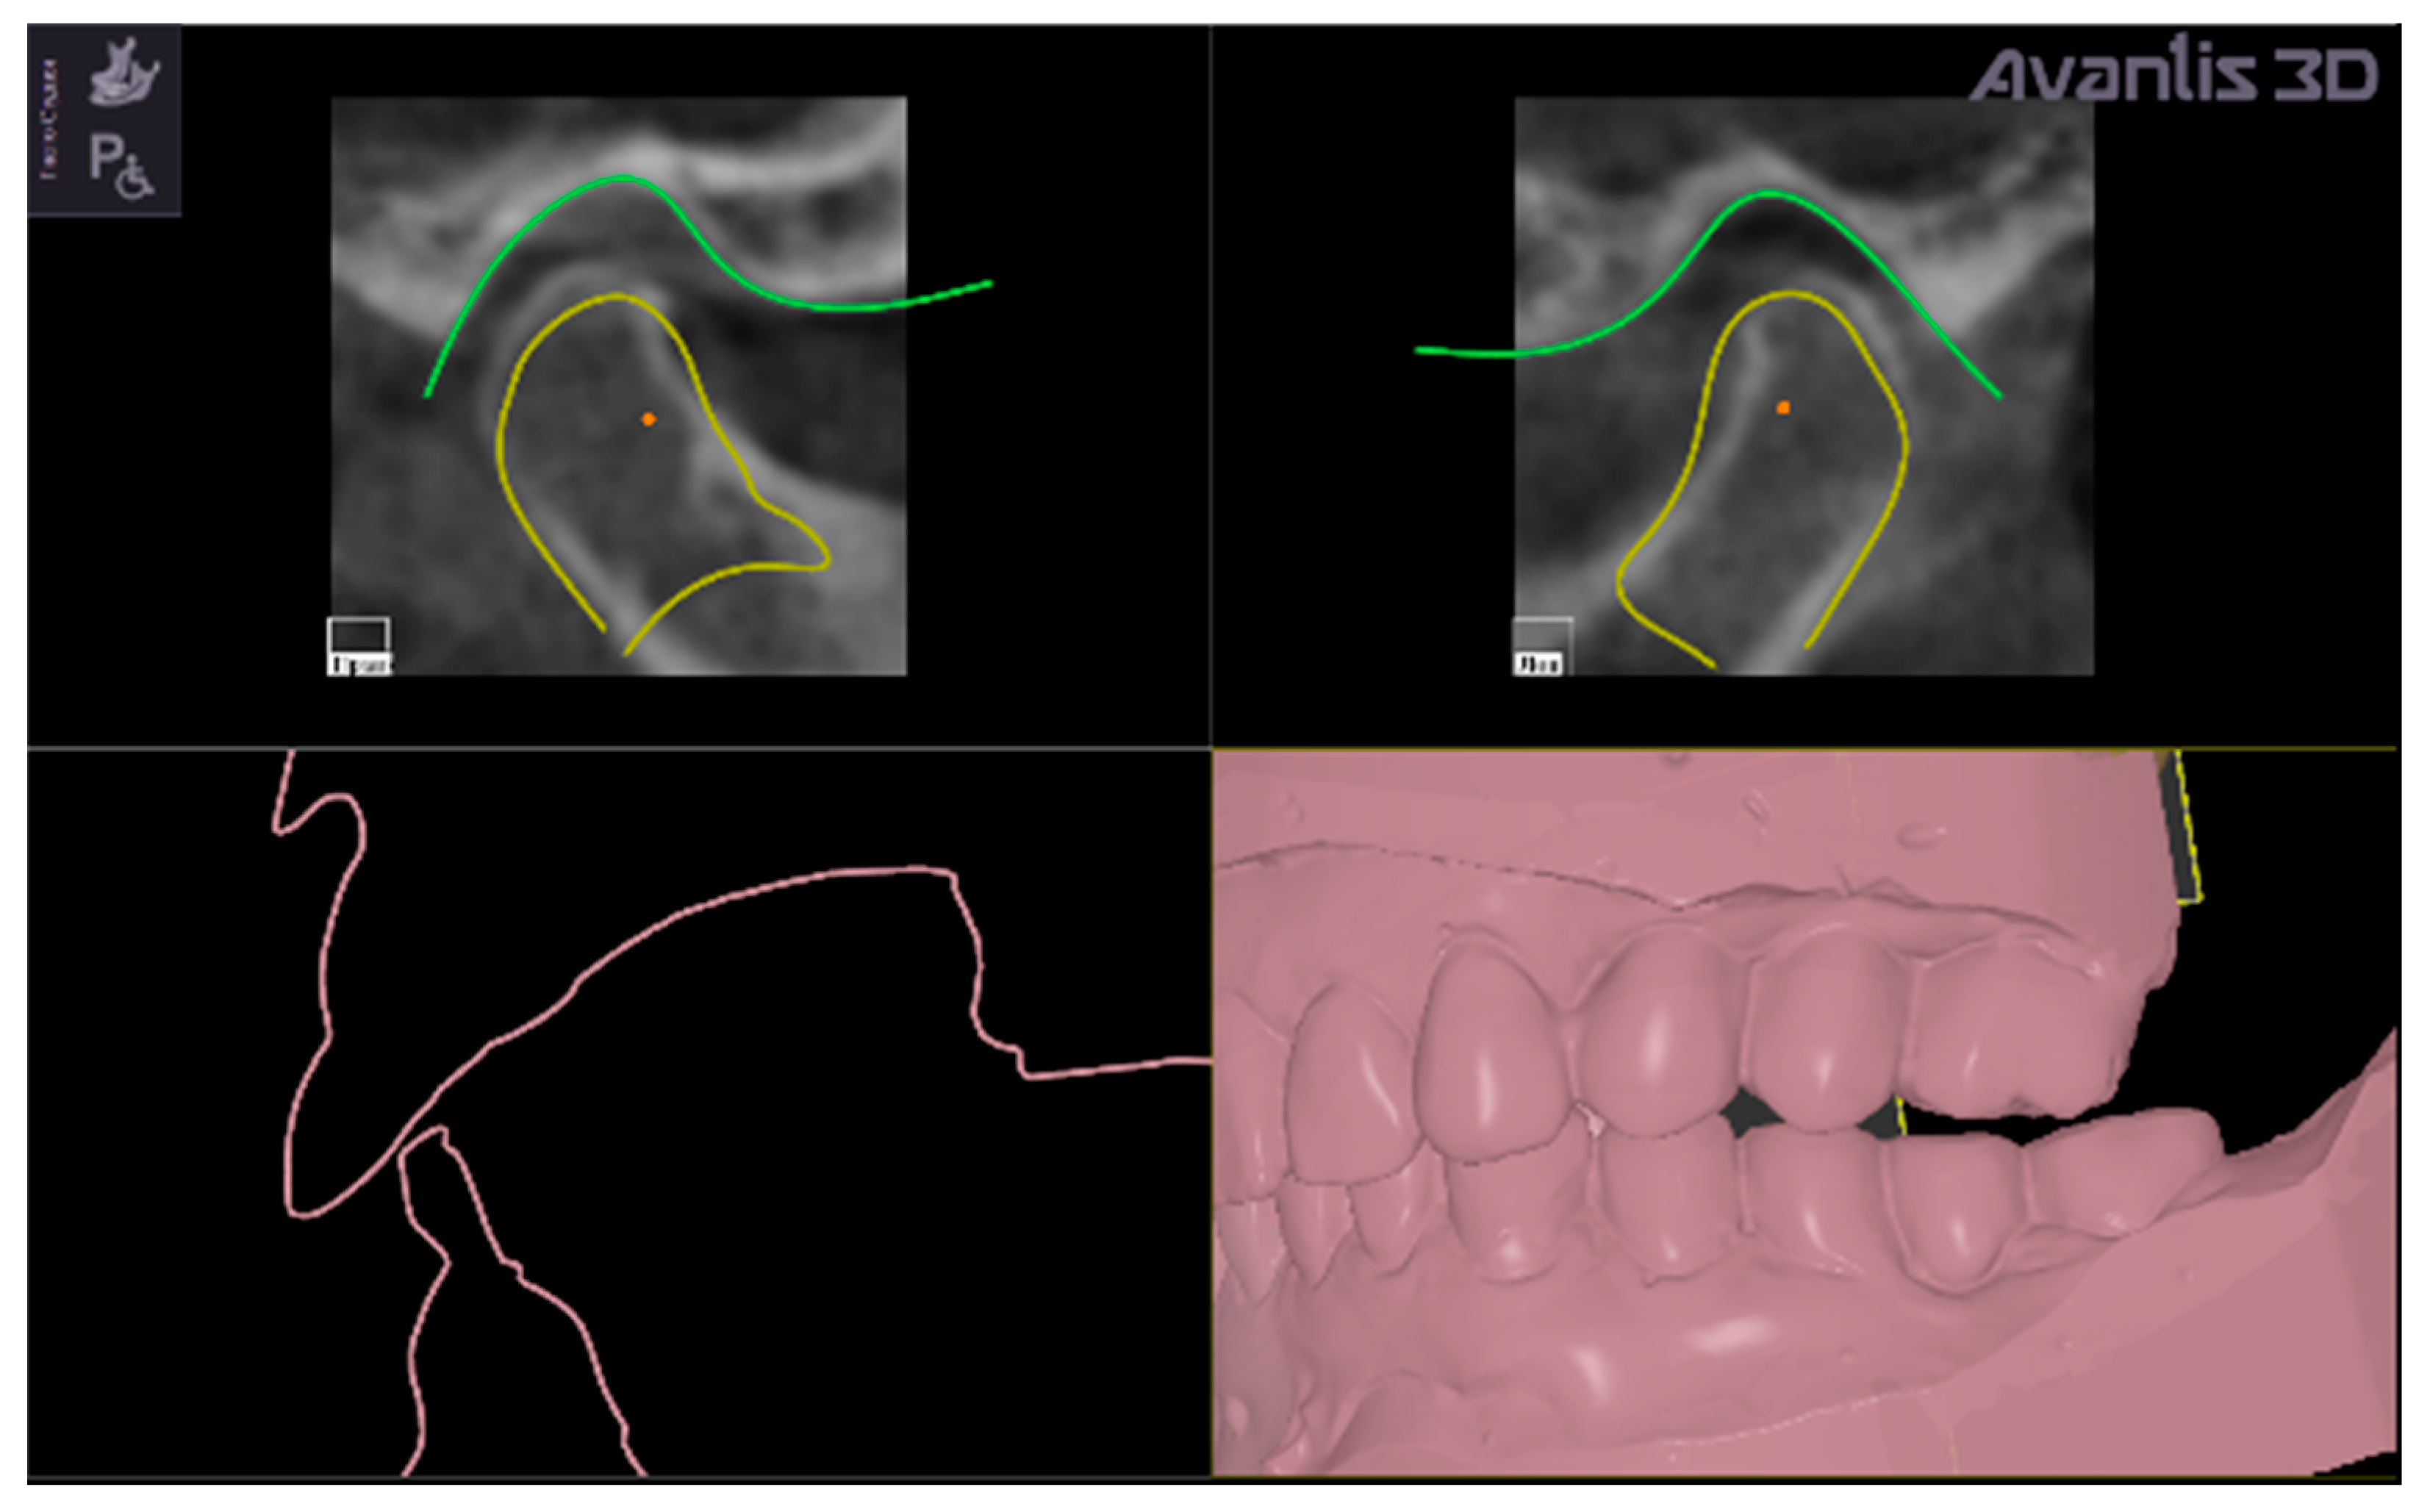

• Selection of condyles and TMJ fossa from CBCT data (Figure 3).

• Mesh triangulation, to reproduce surfaces of condyles and articular fossa.

The new occlusal vertical dimension was then established by lower jaw rotation around a virtual hinge axis passing through the middle points of the condyles (Figure 5 evidences two red points that are the middle points of the condyles).

The middle points of the condyles (represented as red points in Figure 5) are determined automatically by the software on the CBCT 3D reconstruction, connecting the right and left poles of each condyle, thus individuating the middle point of the major condylar axes.

Figure 5. Representation of the virtual shifting of the condyles to normalize the values of the intra-articular space width (yellow contours) and degrees of rotation around intercondylar axis (the virtual hinge axis is the line passing through the red points in condylar heads) to establish the new vertical occlusal dimension (evidenced by pink contour) that is represented as a gap between upper and lower digital models, which will be filled by the virtually designed intra-oral repositioning splint.